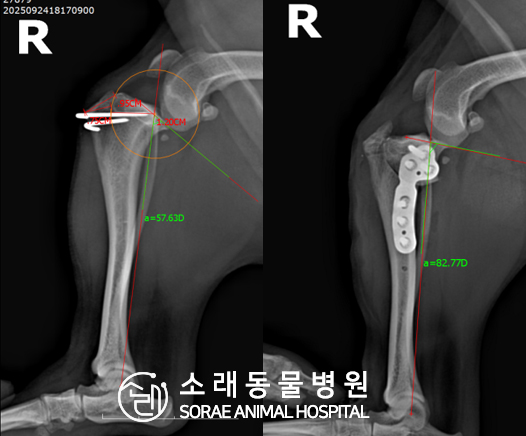

계산식으로 사전에 계획해두었던 플랜에 따라 경골을 절제하고

플레이트와 스크류를 사용하여 임플란트를 적용해 주었습니다.

반대 방향으로 밀려나 어긋나있던 대퇴골과 정강이가

제 자리를 찾으면서 무릎의 각도가 교정된 것을 확인할 수 있습니다